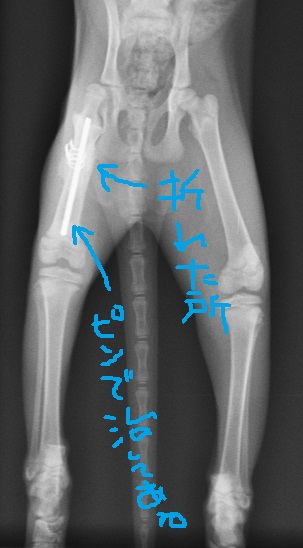

右足の骨折と皮膚が剥けるほどの火傷をおって病院に運び込まれた子です。

なので、スケルトンにするとこんな感じのカワイコさん。

エンジンかけた瞬間、ビックリして飛び起きてベルトに巻き込まれて火傷と骨折…